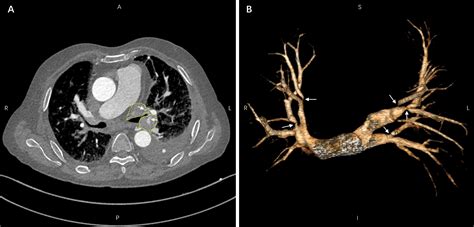

• Imaging Tests: Various imaging tests can help visualize the pulmonary veins and detect any narrowing or blockages. These tests may include:

Computed Tomography (CT) Scan Provides detailed images of the pulmonary veins and surrounding structures, helping to identify the location and extent of stenosis.